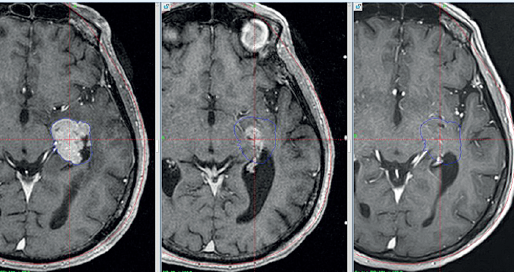

Например, единичные метастазы печени можно удалить различными способами – хирургическое иссечение, тепловая деструкция под действием лазера или радиоволн, с помощью химиоэмболизации опухоли и др. При единичных метастазах в головной мозг и легкие может применяться гамма-нож или хирургическое лечение.